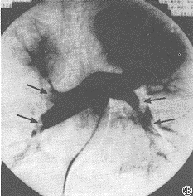

发生率约75%。开始于缺氧导致的呼吸急促及随后的过度换气,紫绀有时不会出现,但有时可能成为FES的早期体征。涉及肺的FES病人大部分PaO2水平低于6.67kPa,如果肺的条件恶化,就可能合并呼吸困难和代谢性酸中毒。部分病人有咯血。胸部X线片示两肺大块斑片状阴影,称之为“暴风雪样”改变,尤其在肺的上中部多见。

1.主要标准 (1)皮下出血:可在伤后2~3天左右,双肩前部、锁骨上部、前胸部、腹部等皮肤疏松部位出现,也可见于结膜或眼底,伤后1~2天可成批出现,迅速消失,可反复发生。因此,对骨折病人入院数天内应注意检查。 (2)呼吸系统症状:主要症状为呼吸困难、咳嗽、咳痰(经常有血性),但湿性啰音不是特有症状。典型肺部X线可见全肺出现“暴风雪”状阴影,并常有右心负荷量增加的影像。但这种阴影不一定都能发现,而且如无继发感染,可以很快消失。因此,对可疑病例,可用轻便X线机反复检查。 (3)脑症状:主要表现为头痛、不安、失眠、兴奋、谵妄、错乱、昏睡、昏迷、痉挛、尿失禁等症状。虽很少出现局灶性症状,但偶然可有斜视、瞳孔不等 大及尿崩症等,因此,当有些骨折病例出现难以解释的脑症状时,应怀疑脂肪栓塞。